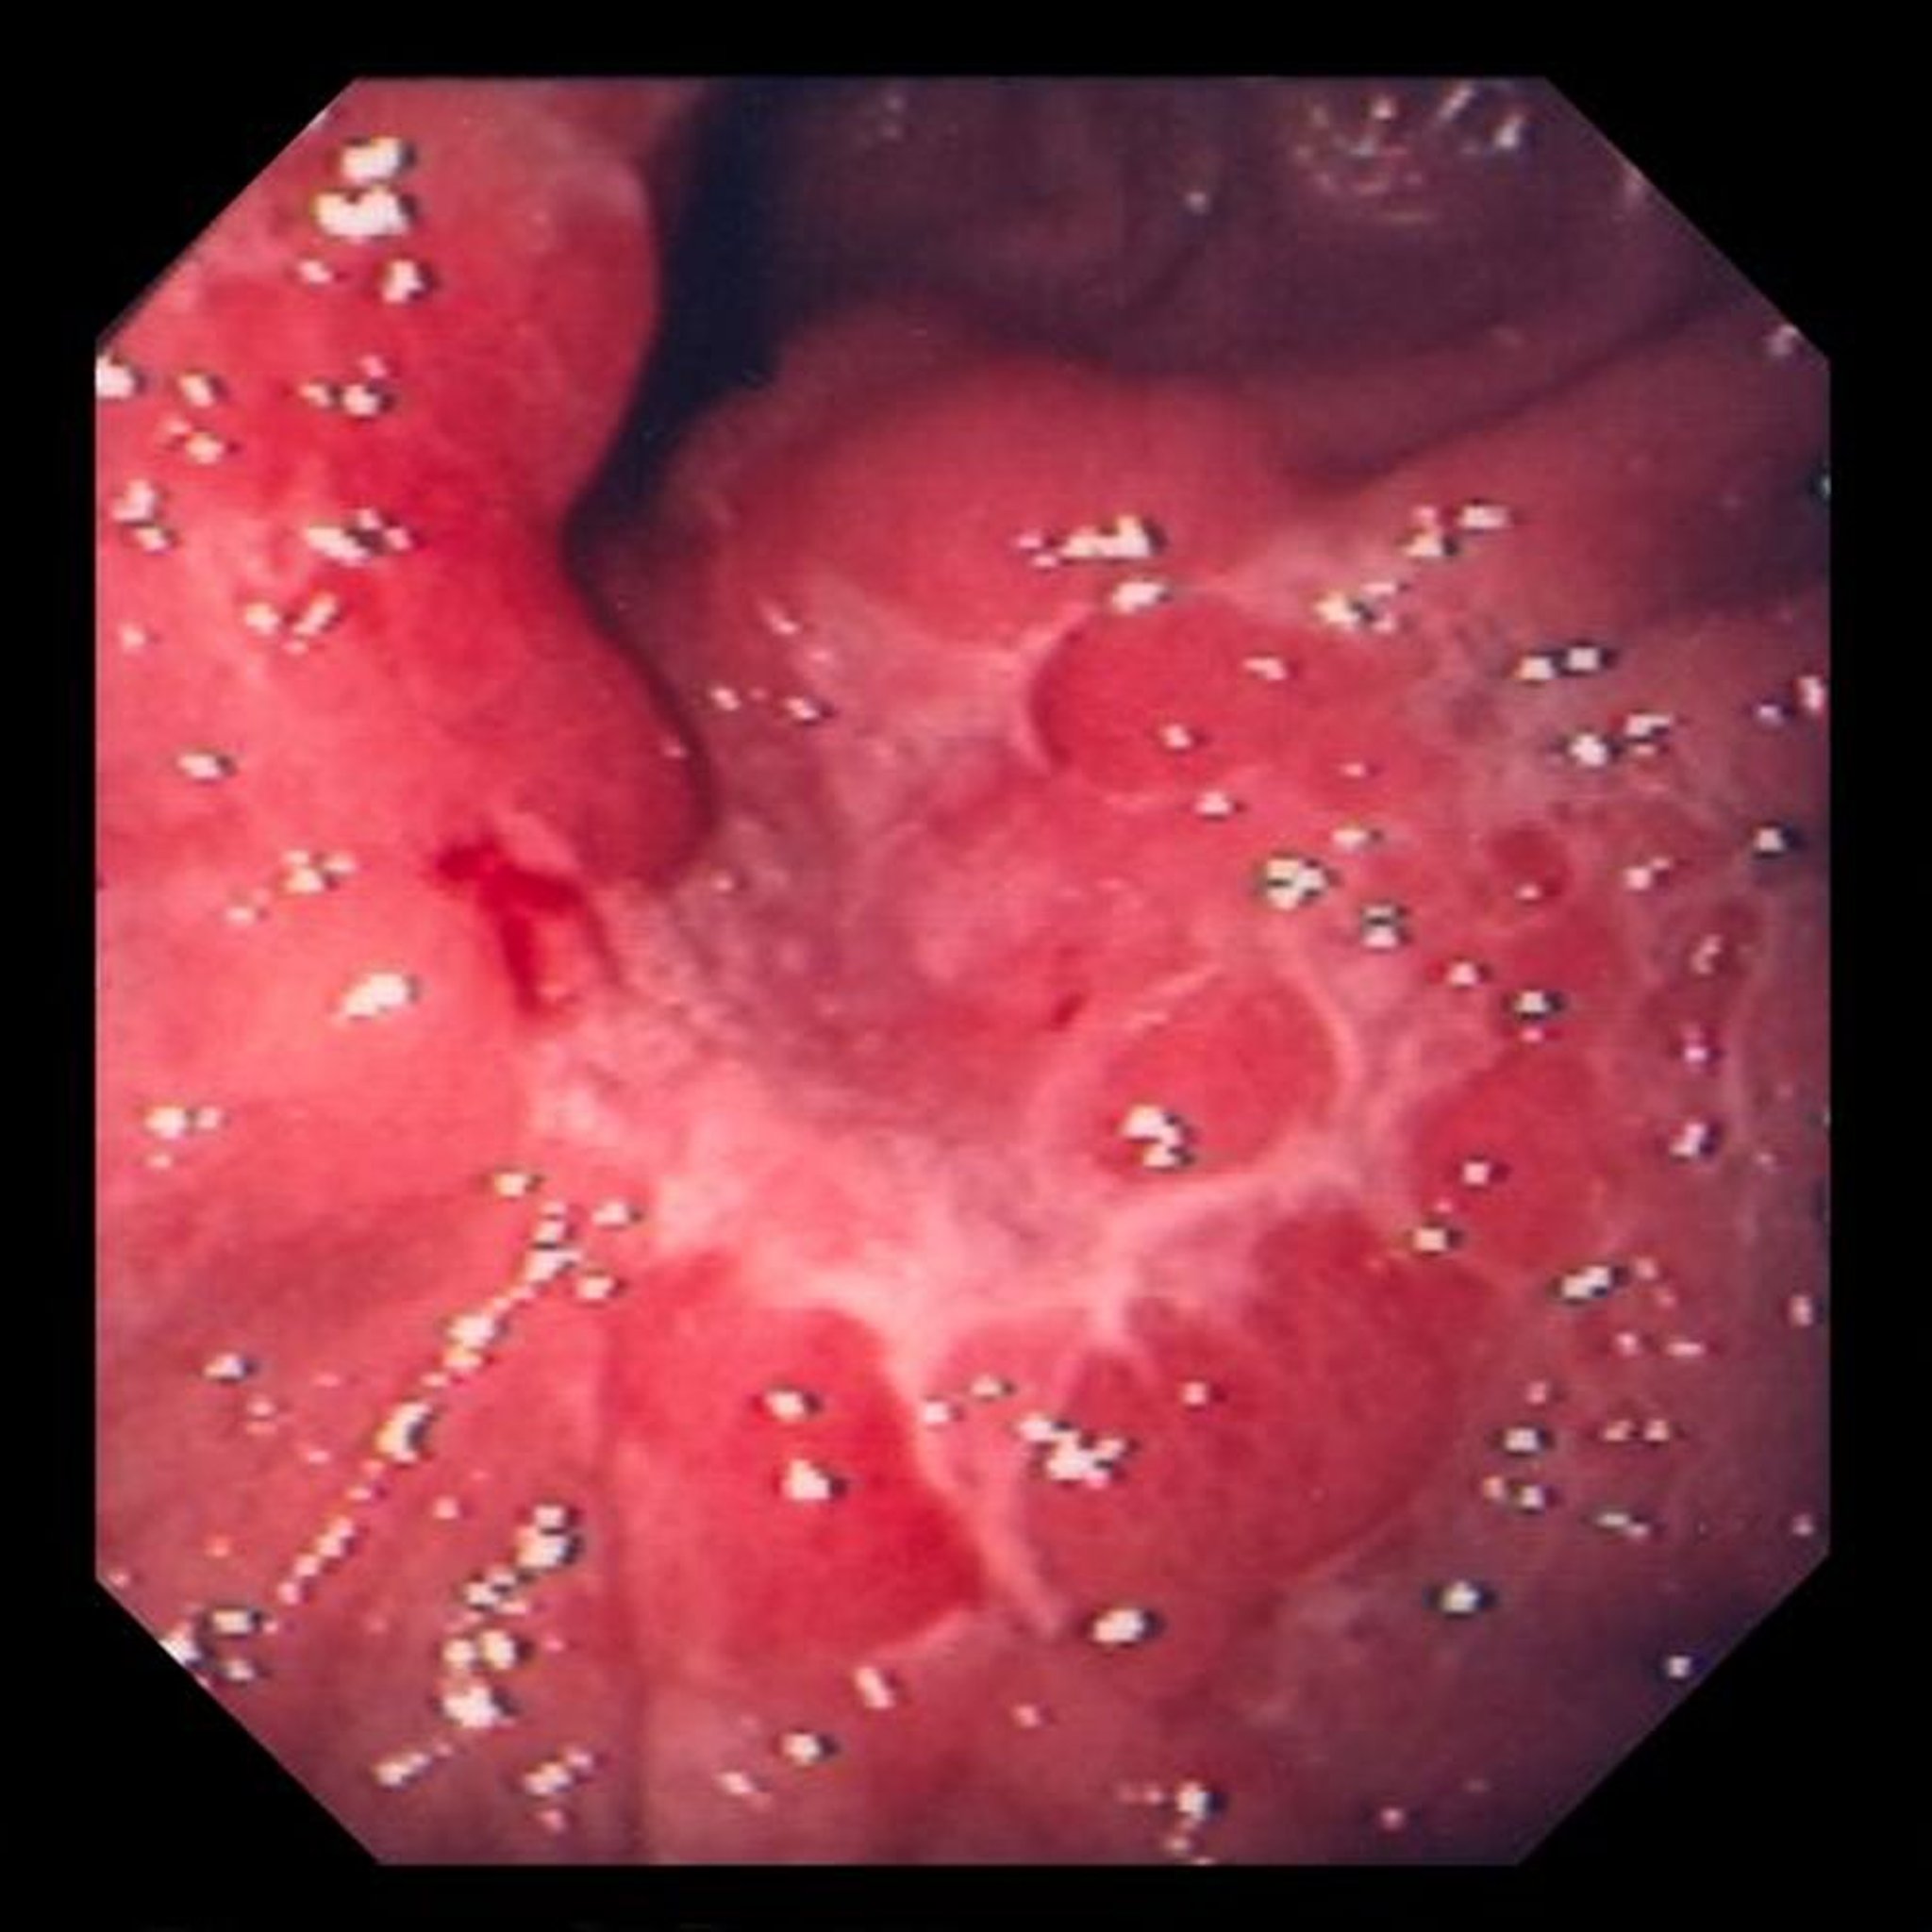

На этом изображении показана язва в отечных складках слизистой, оказавшаяся по результатам биопсии малодифференцированной аденокарценомой (перстневидноклеточного типа).

Image provided by David M. Martin, MD.